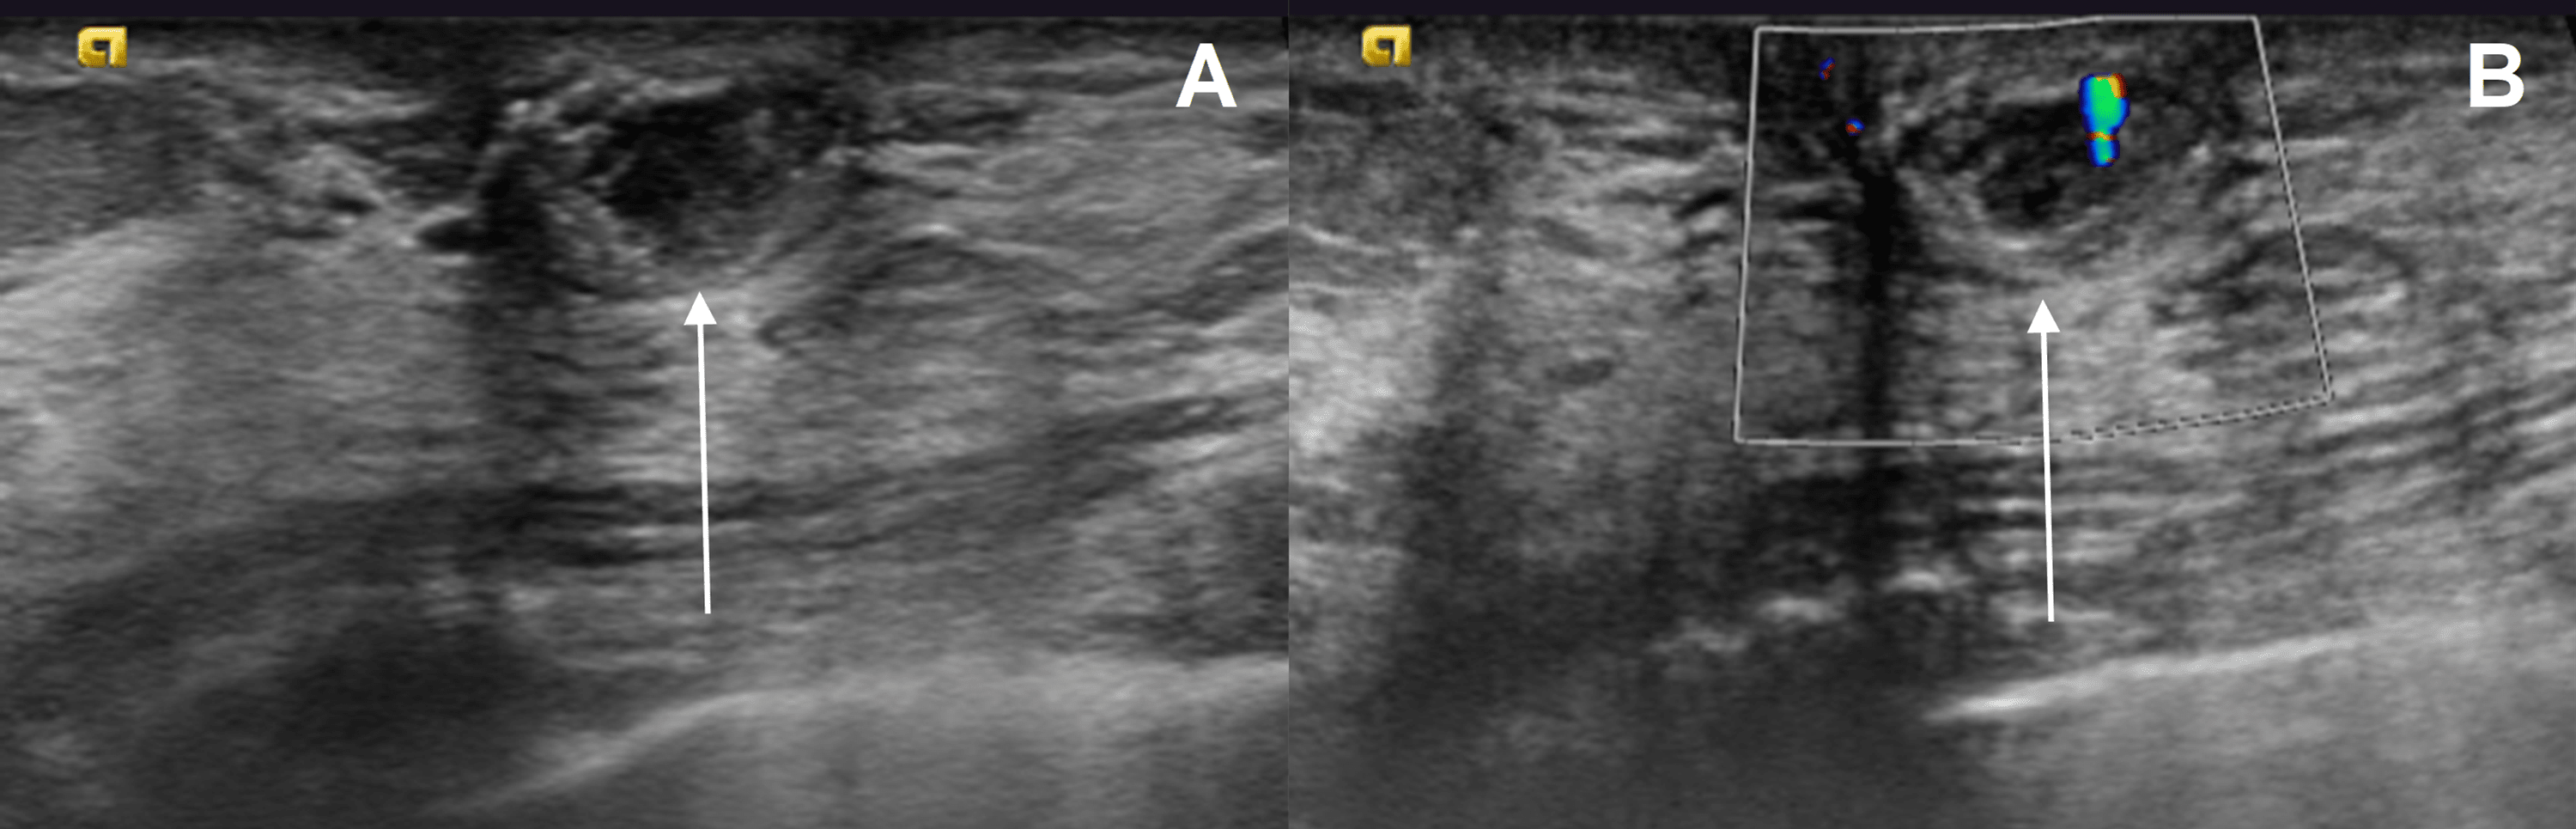

Normal testis (A) and abnormal testicular (B) echotexture. Patient 1 Uniform Increase In Echotexture Coarsened hepatic echotexture is a sonographic descriptor used when the uniform smooth hepatic echotexture of the liver is lost. Liver echotexture conclusion when characterizing liver echotexture on us, the use of the spleen as an internal comparison improves. Normal liver tissue appears homogeneous on ultrasound, meaning it has a uniform echo pattern. Coarsened hepatic echotexture is a sonographic descriptor used. Uniform Increase In Echotexture.